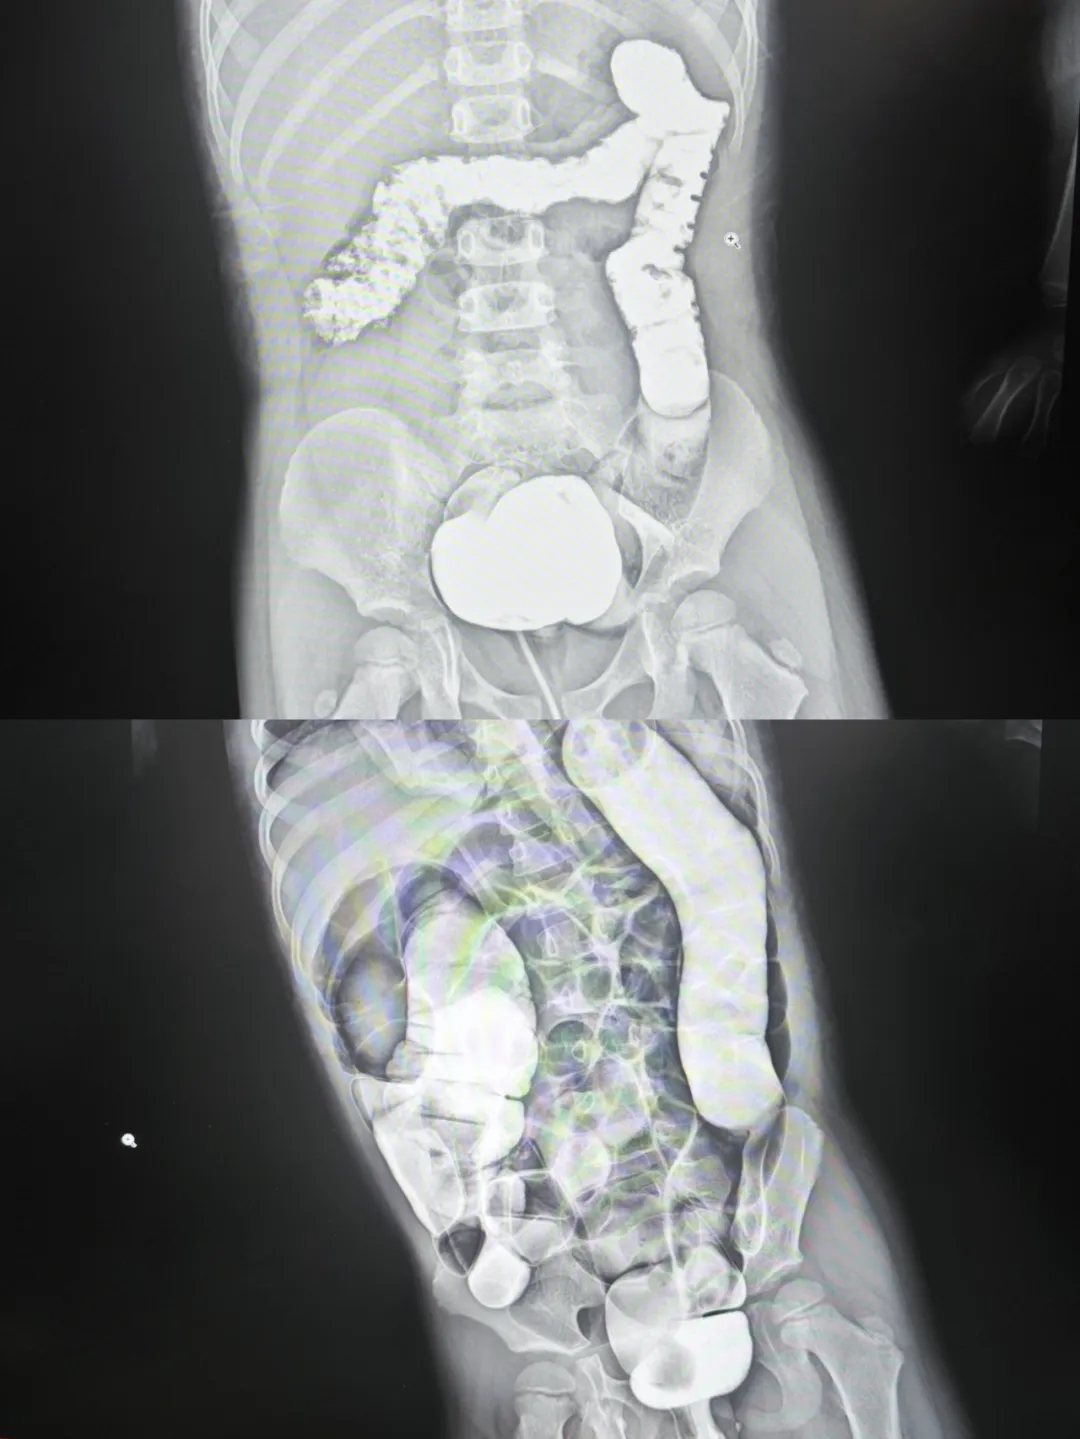

病例2

回盲部复位、小肠逆行充气,复位成功